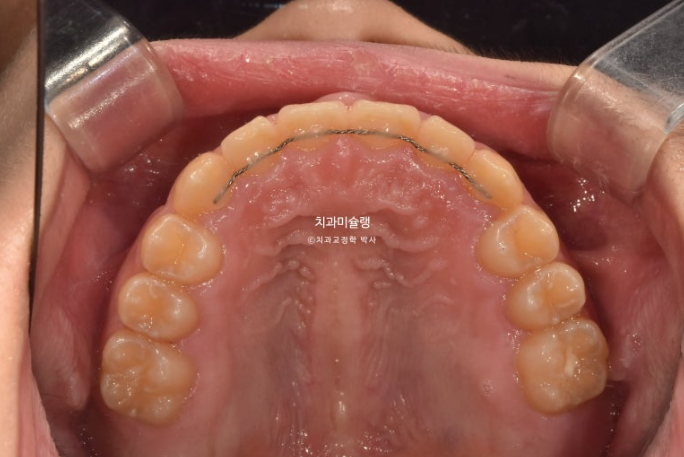

인비절라인퍼스트 치료에 들어갔고 24년 4월까지, 첫세트의 21개 장치를 모두 낀 후 모습입니다.

24.04

과개교합의 개선

배열의 개선

이제 막 남아있던 유치들이 빠지고 영구치가 나오는 시기라 전략적으로 쉬는시간을 갖습니다.

21번 장치를 잘때만 끼면서 영구치 맹출을 기다리는 시간이죠.

24년 10월까지 6개월간 남은 영구치 맹출을 기다립니다.